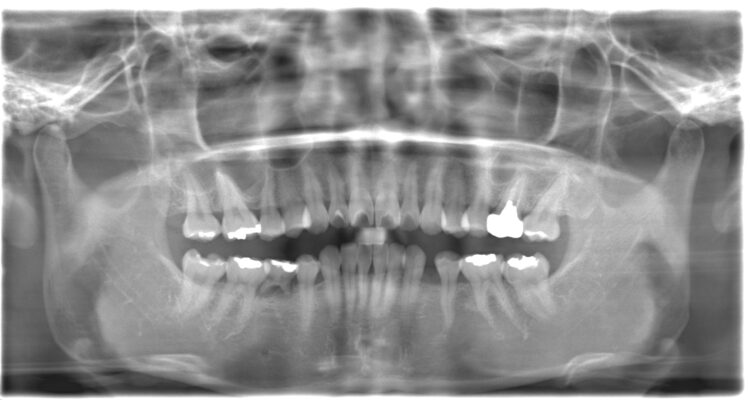

初診時